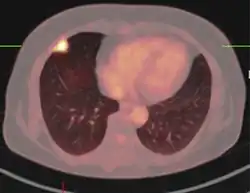

PET scan

If there is an intermediate risk of malignancy, further imaging with positron emission tomography (PET scan) is appropriate (if available). It can be done simultaneously as a CT scan in the form of PET-CT. Around 95% of patients with a malignant nodule will have an abnormal PET scan, while around 78% of patients with a benign nodule will look normal on PET (this is the test sensitivity and specificity).[15] Thus, an abnormal PET scan will reliably pick up cancer, but several other types of nodules (inflammatory or infectious, for example) will also show up on a PET scan. If the nodule has a diameter of less than one centimeter, PET scans are often avoided because of an increased risk of falsely normal results.[15][16][17] Cancerous lesions usually have a high metabolism on PET, as demonstrated by their high uptake of FDG (a radioactive sugar).

PET-CT of a tuberculoma.

PET-CT of a tuberculoma.